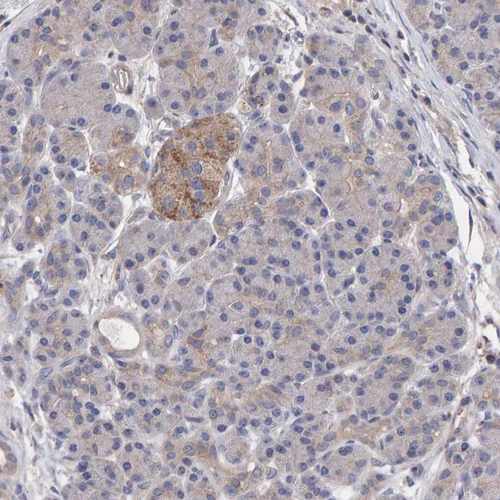

Immunohistochemistry analysis in human cerebral cortex and pancreas tissues using Anti-EFR3A antibody. Corresponding EFR3A RNA-seq data are presented for the same tissues.